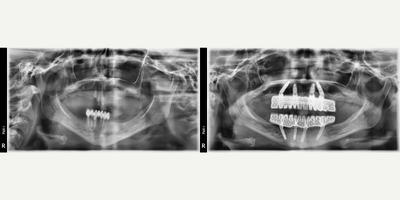

55-64 year old man treated with All-on-4 Dental Implants, Dental Implants

Our patient had severe periodontal disease and all teeth needed to be extracted.Allon4 for upper and conventional 6 dental implants for lower have been performed.